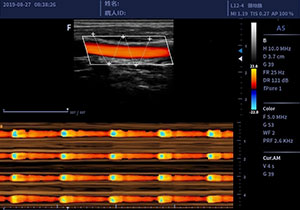

• L12-4/L12-5线阵探头

适用于外周血管、小器官、神经肌骨等

临床超声检查

彩色M成像